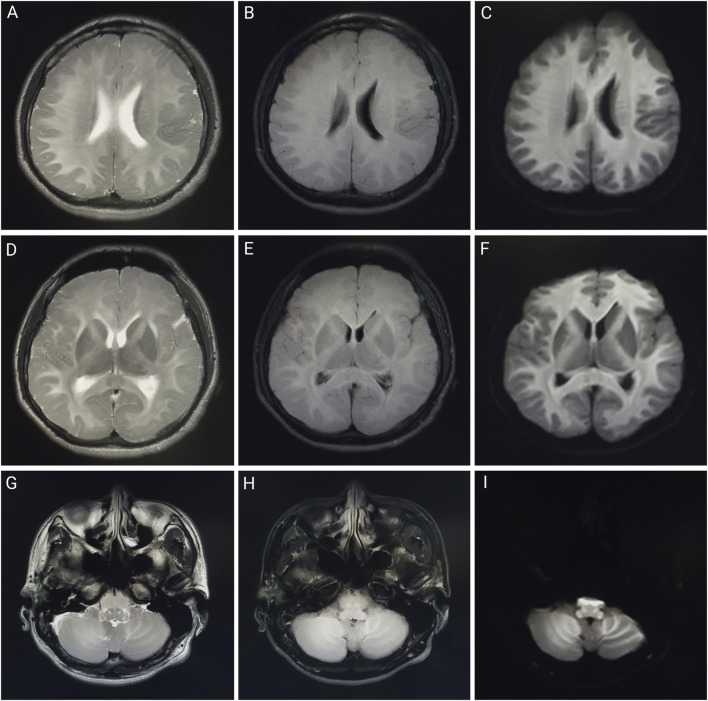

Results: All four patients worked in the same factory before admission; three worked in the same workshop, while one worked in the product inspection department. Patients three and four had no obvious clinical manifestations, whereas patients one and two primarily presented with hyperhidrosis, fever, and neurological symptoms. Laboratory tests revealed abnormalities in blood counts, liver and kidney function indicators, and cardiac enzyme profiles in some patients. Magnetic resonance imaging revealed varying degrees of abnormal signal changes in the brain and spinal cord in Patients 1, 2, and 3. After comprehensive treatment with blood purification, organ protection, and symptomatic treatment, chlorfenapyr blood concentrations in patients 1, 2, and 3 decreased. Patients one and three were discharged on the 30th and 14th days of admission, respectively, while patient 2, whose condition worsened, died on the 11th day of treatment after unsuccessful resuscitation.

Abstract Image